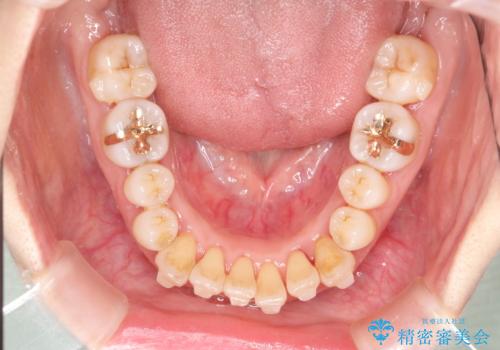

インビザラインによる矯正治療(非抜歯) 上下前歯の開き(開咬)と上下のガタつき(叢生)の改善

- 上下の前歯の開き(開咬)と上下前歯にガタつき(叢生)が見られます。

マウスピース枚数 初回36枚 + 追加26枚

概ね1年4ヶ月で治療完了しました。

マウスピース矯正は開咬(オープンバイト)に対して有利な治療メカニクスを持ちます。

当院独自の工夫を随所に盛り込み、狙い通りの治療結果が得られました。